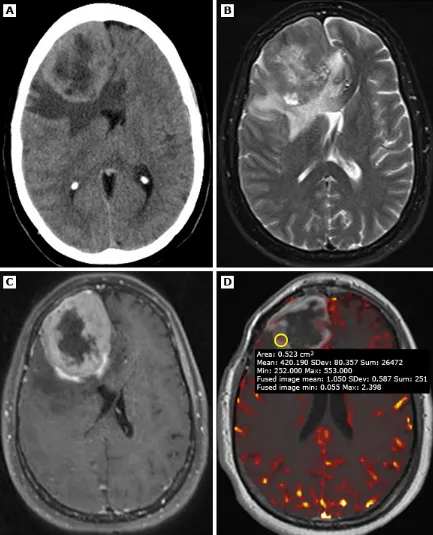

一名49歲患者,經(jīng)病理證實(shí)為3級(jí)(間變性)腦膜瘤

一名49歲患者,經(jīng)病理證實(shí)為3級(jí)(間變性)腦膜瘤。A(平掃頭顱CT):顯示右側(cè)額葉巨大占位性病變,密度不均,周圍伴血管源性水腫,并導(dǎo)致明顯占位效應(yīng)。B(橫軸位T2加權(quán)MRI):腫塊呈不均勻信號(hào)強(qiáng)度,周邊可見相對(duì)于高信號(hào)核心的厚壁低信號(hào)環(huán)。C(增強(qiáng)后MRI):強(qiáng)化腫塊內(nèi)部可見中央強(qiáng)化減低區(qū),提示存在中央壞死。D(灌注加權(quán)MRI):相對(duì)腦血容量(rCBV)未見升高。